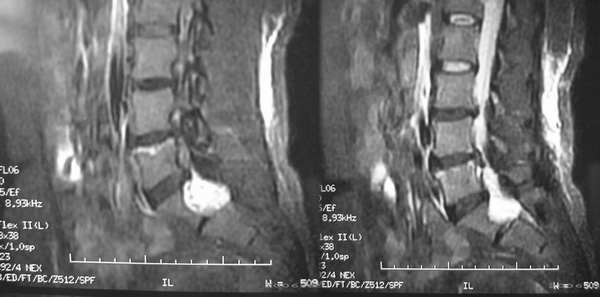

患者,女性,60岁。腰痛、腿痛一周余,临床医生考虑:椎间盘突出,行ct及mr检查

病灶为长t1长t2信号,对s1椎体是压迫吸收,应首先考虑骶管囊肿。建议增强扫描。

征象:1、骶椎管偏右侧囊性病变,长t1长t2改变,均匀。2、慢性病变过程,邻近骨质有吸收变薄。

考虑:盲囊蛛网膜囊肿。

S1椎长T1长T2信号,与蛛网膜下腔相连,边界清晰,CT可见局部骨质吸收,边缘硬化改变。支持骶管囊肿。